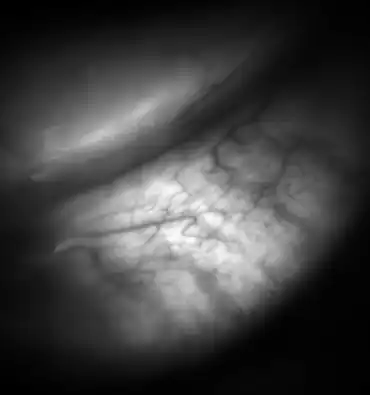

Meibomian glands in the lower eyelid imaged under amber light to show vasculature support and the gland structure [epiCam].

Meibomian glands in the lower eyelid imaged under amber light to show vasculature support and the gland structure.